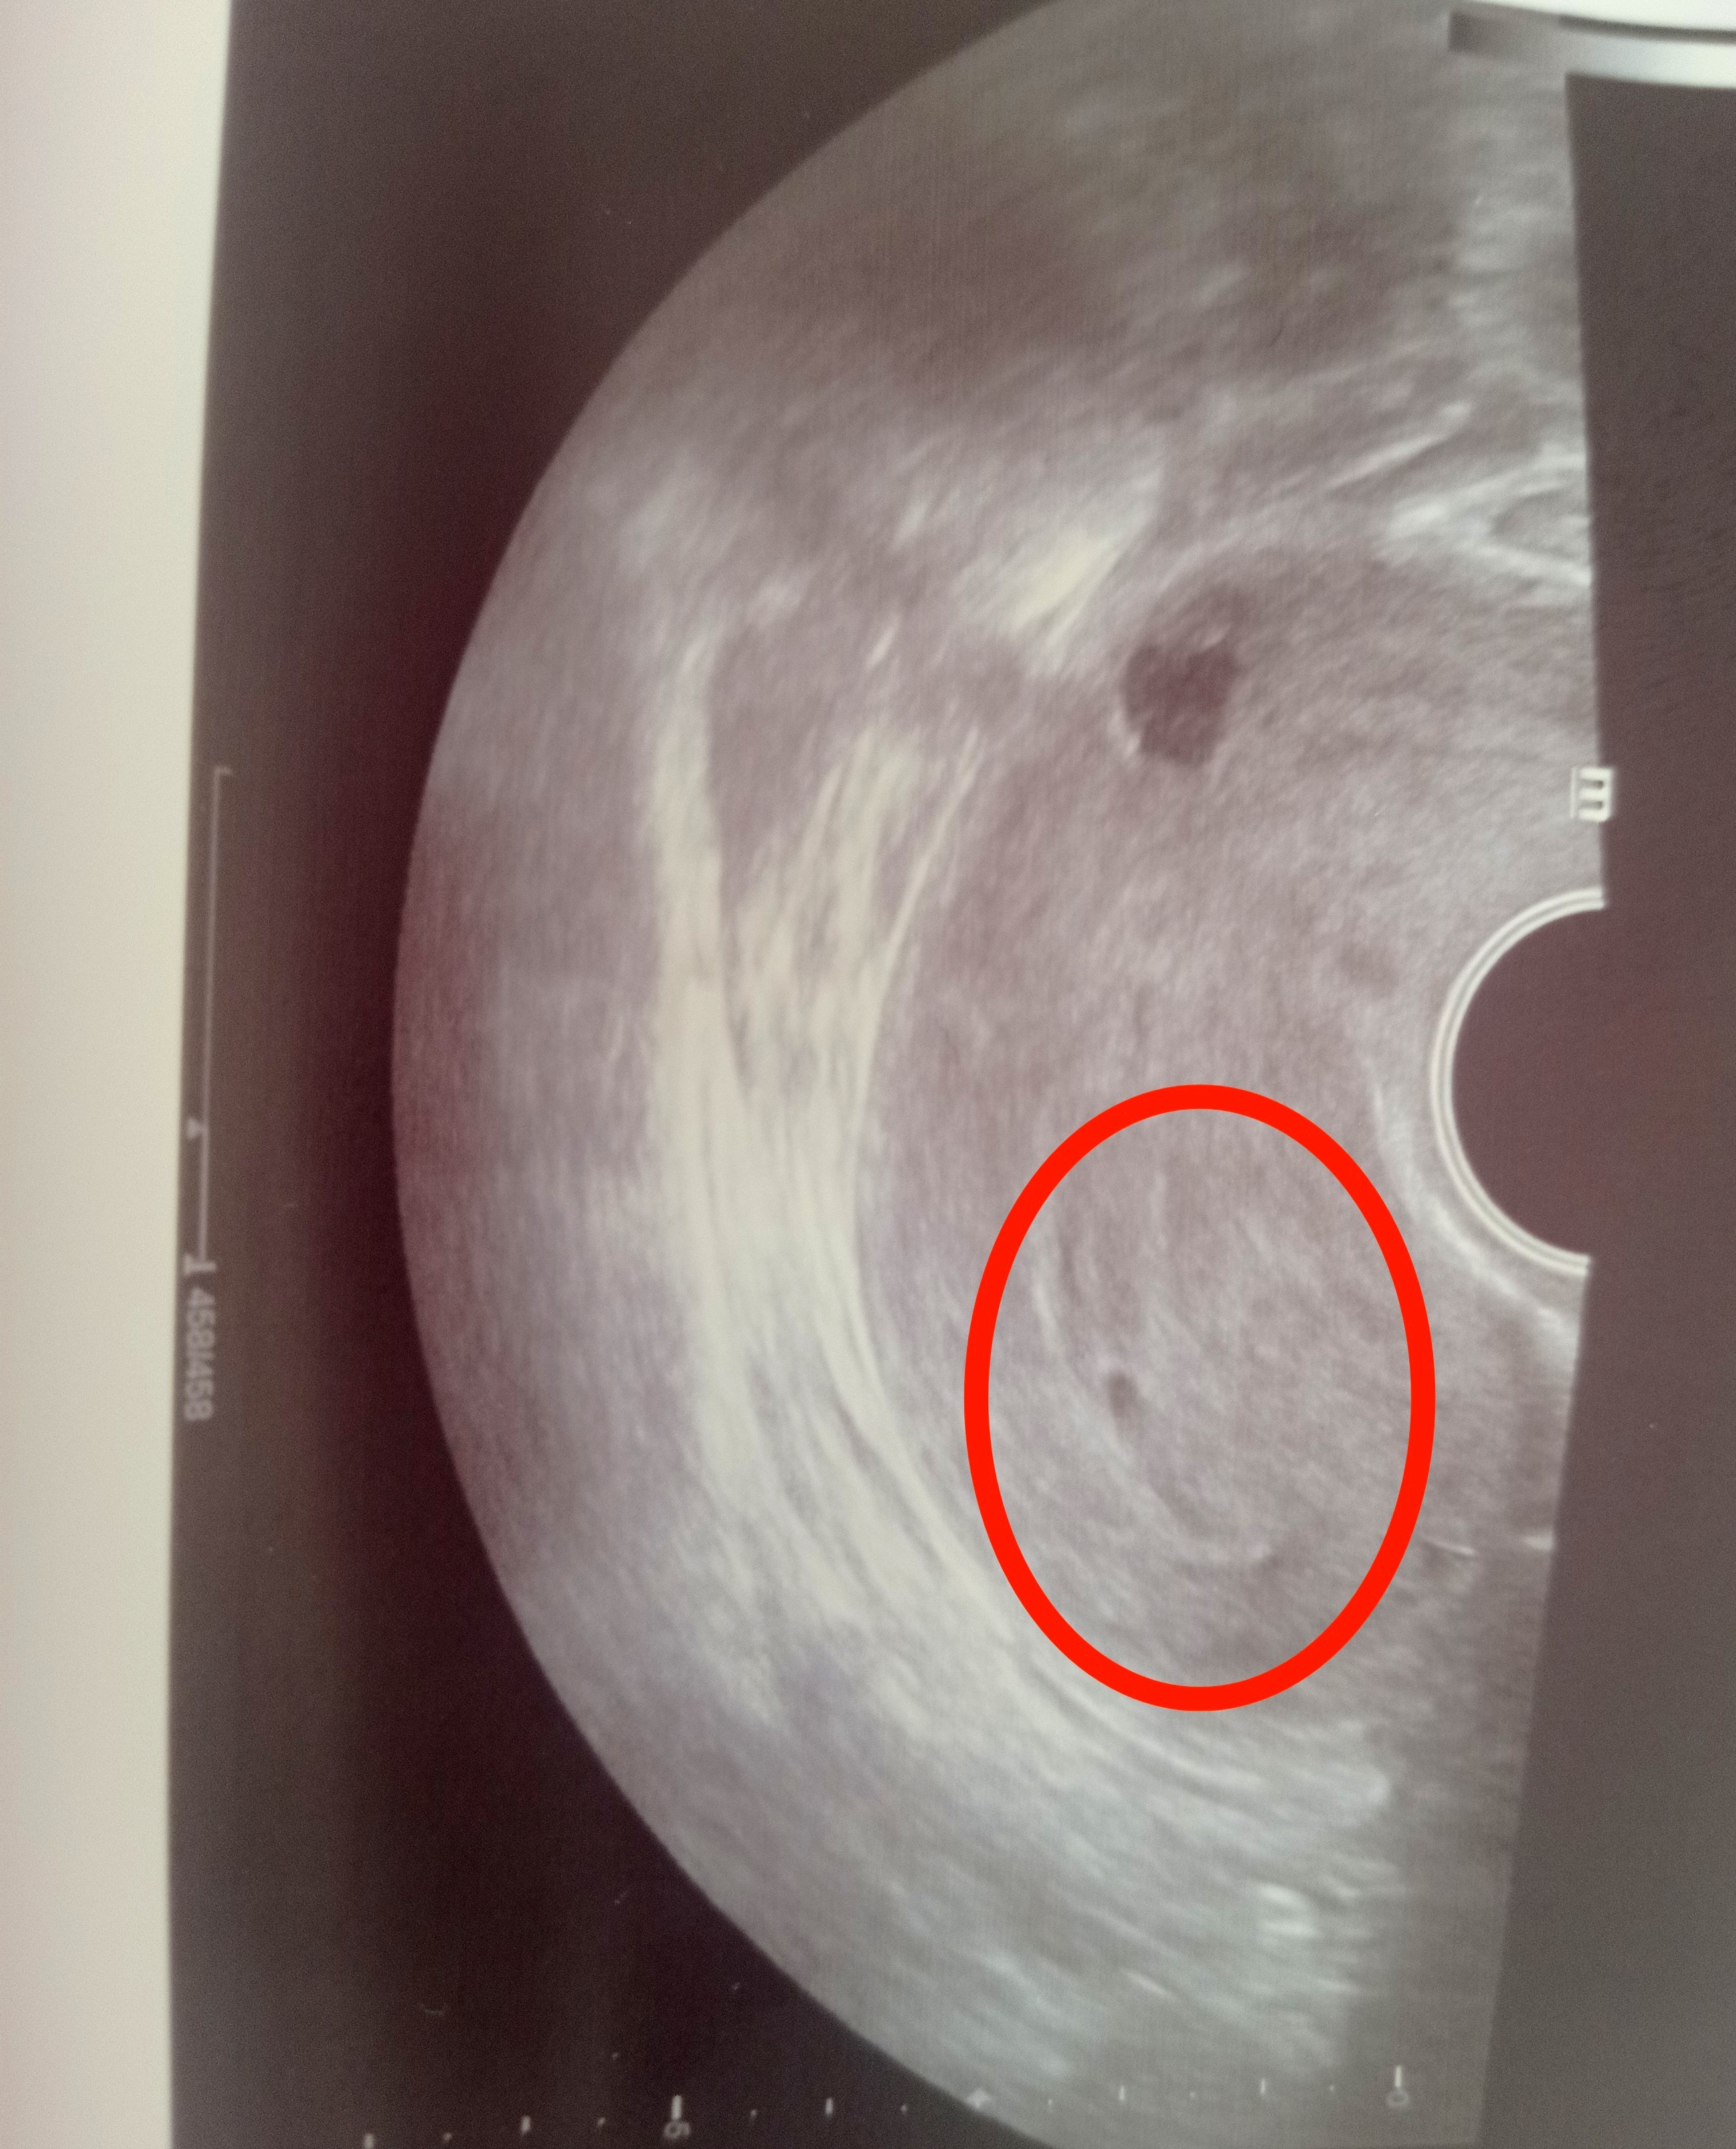

Nie odbieram nic jako atak, też nie liczę się z tym że się utrzyma ciąża. przesyłam zdj pęcherzyka. Zaznaczam to jest tylko pęcherzyk, w nim musi się pojawić ciałko a potem dopiero zarodek.

Załączniki

• IMG_20220420_165307.jpg

IMG_20220420_165307.jpg

1,6 MB · Wyświetleń: 234